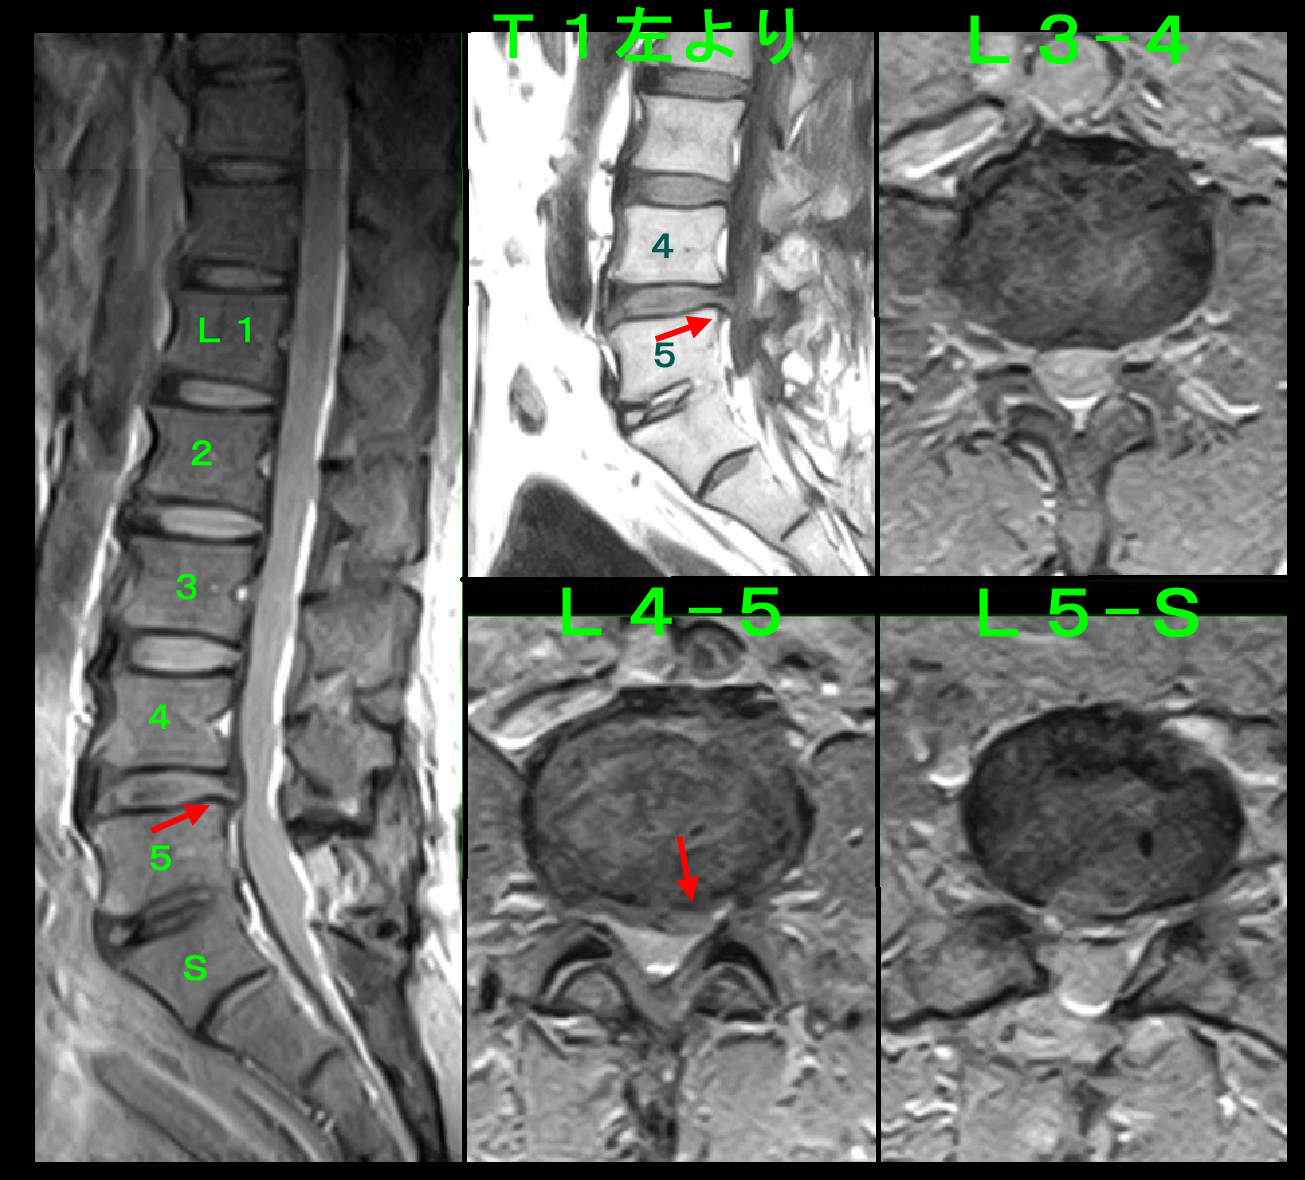

26才の工場に勤務する派遣社員の女性の患者さんです。20年前の症例のため、画像資料はMRI画像しか残っていません。平成18年4月20日に当院を受診されました。1か月前から腰痛があり、4月19日から作業困難となり、会社近くの整形外科を受診し、投薬とコルセットの装着をうけましたが、効果がないため知人の勧めで遠くから当院を受診されました。前かがみでやっと歩いている状態でした。

腰椎MRI検査ではL5Sに中等度の椎間板ヘルニアを認めます。同日、両側L5S高位で神経根ブロックを施行し、鎮痛剤の処方をしています。当時の評価は最初の痛みをVAS10として評価してもらっています。1週後の4月27日の再診ではVAS10→5に軽減していました。同日2度目の両側神経根ブロックを施行しました。ゴールデンウイークの期間ですから、工場は長期の休みになります。5月4日に出勤に向けて半日立位や座位の練習をしたところ、腰痛は悪化し、医大を受診したそうです。医大では仙骨裂孔ブロック(という当院とは異なるブロック)を受けて、5月5日には1日臥床して腰痛は軽減したそうです。5月6日に3回目のL5S高位の神経根ブロックを行い、ゴールデンウイーク期間の経過から、5月いっぱい休んだ方が無難ではないかとアドバイスし、2週間の処方を行いました。5月20日の受診時に患者さんは「5月10日から出勤したが、仕事はできている。」と報告してくれました。私のアドバイスは役立ちませんでした。